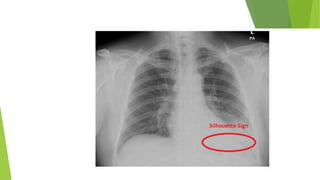

† Loss of aeration. If the collapsed lung is adjacent to the mediastinum or

diaphragm, then loss of definition of these structures indicates loss of

aeration (the silhouette sign).

Note the loss of the right heart border silhouette

due to partial atelectasis of the RML